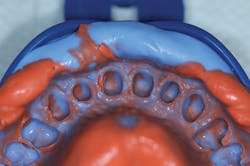

Once it was determined that the gingiva and soft tissue were healthy, a system of VPS impression materials was used to capture a final impression of the prepared teeth. A cordless impression technique was employed to accurately capture fine detail. In this technique, known as a hydraulic hydrophobic impression,2,3 a base VPS impression material was used (V-Posil Putty Fast, Voco) in order to capture the preliminary phase of the two-step impression (figure 5). Once completely set, the impression was removed, rinsed, and dried, and a light-body VPS impression material (V-Posil Light Fast, Voco) was injected into the entire intaglio of the base VPS (figure 6).

Figure 5: Phase one of impression